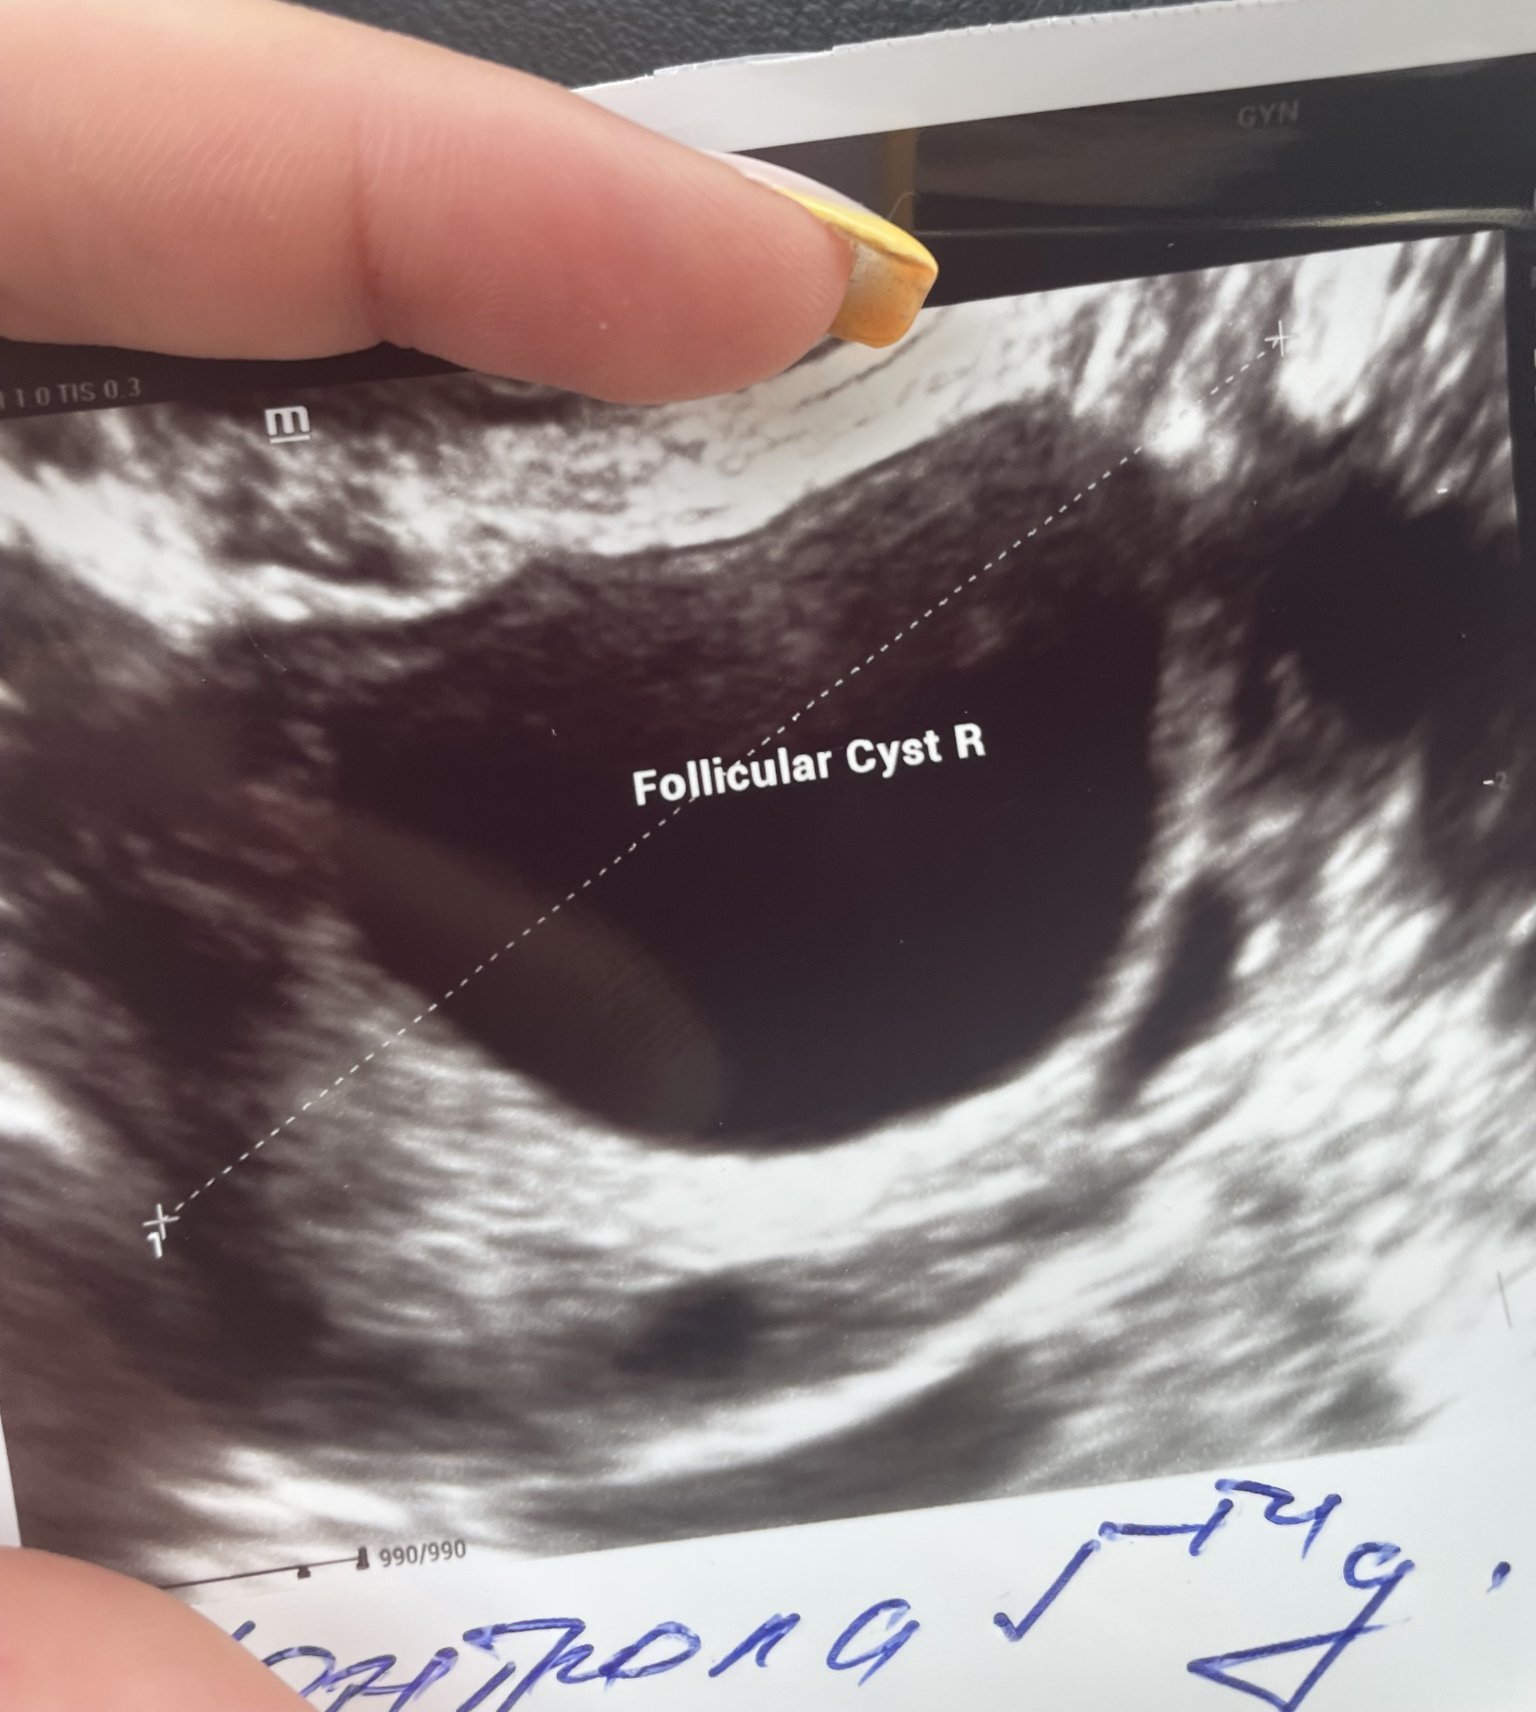

Различните кисти на яйчниците са течности или твърди образувания, които се развиват в яйчниците. Те могат да бъдат функционални, фоликуларни, ендометриозни, параовариални и други. Функционалните кисти възникват по време на нормалния цикъл на функциониране на яйчниците, докато другите видове кисти могат да бъдат свързани с различни заболявания или състояния.

За да се определи дали киста на яйчника е злокачествена или доброкачествена, се извършват различни тестове. Тези тестове включват ултразвук, ЯМР и кръвни изследвания като CA-125, HE4, ROMA и други. Нормалните стойности на тези тестове обикновено показват липса на злокачествено заболяване; обаче окончателната диагноза се поставя от специалист след преглед на резултатите.